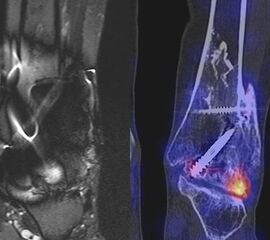

Beispiele für SPECT/CT-Untersuchungen nach OSG-TEP sind in den Abbildungen 6.1. bis 6.3. abgebildet.

Gurbani et al. evaluierten 37 Patienten mit schmerzhaften Sprunggelenkprothesen mit SPECT/CT und korrelierten die Ergebnisse mit klinischen und intraoperativen Befunden. Die SPECT/CT-Ergebnisse korrelierten zu 89,2 % (33/37 Pat.) mit der definitiven Diagnose. 28 Patienten wurden operativ revidiert und der Vergleich der SPECT/CT-Befunde mit den intraoperativen ergab eine Übereinstimmung von 92,9 % (26/28 Pat.). Die SPECT/CT identifizierte in den meisten Fällen aseptische Lockerungen (12/33 Pat.) und Impingement (11/33 Pat.). Seltenere Diagnosen waren Fehlstellungen (4/33 Pat.), Zystenbildungen (2/33 Pat.), subtalare Arthrosen (2/33 Pat.) und Infektionen (2/33 Pat.) 51.

Die Autoren beschreiben einen Fall, der neben einem Fokus am lateralen Malleolus auch eine starke flächige Anreicherung am talaren Prothesen-Knochen-Interface 17 Monate nach TEP-Implantation aufwies, so dass neben dem Verdacht auf ein laterales Impingement auch der Verdacht auf eine Lockerung der talaren Prothesenkomponente geäußert wurde. Intraoperativ bestätigte sich die Lockerung der talaren Prothesenkomponente nicht, sondern nur das laterale Impingement, welches mittels Debridement erfolgreich therapiert wurde 51. Da der Pat. bereits vor der TEP-Implantation eine Triple-Arthrodese erhalten hatte (welche im SPECT/CT unauffällig war), kann eine solche flächige Mehrspeicherung auch als weitgehend asymptomatische Stressreaktion gewertet werden.

Mertens et al. 52 berichten unter Anwendung eines standardisierten Auswerte-Schemas über eine Treffsicherheit von 96 % (Sensitivität 100 %, Spezifität 80 %) des SPECT/CT zur Diagnose der Ursachen für eine schmerzhafte Sprunggelenkprothese (n=24). Der SPECT/CT-Befund führte in 86 % zu einer spezifischen Therapie, welche in 83 % der Fälle zum Therapieerfolg führte.

Eine Analyse von Mason et al. 53 von 14 Patienten mit schmerzhaften Sprunggelenksprothesen, welche mittels SPECT/CT untersucht wurden, fanden in 13/14 Patienten ein SPECT/CT-Korrelat für die Beschwerden, wobei bei 12 Patienten der Fokus talar medial lokalisiert war. 8 Patienten wurden operativ revidiert und der Fokus entsprach einer verminderten bzw. fehlenden ossären Integration der talaren Prothesen-Komponente.